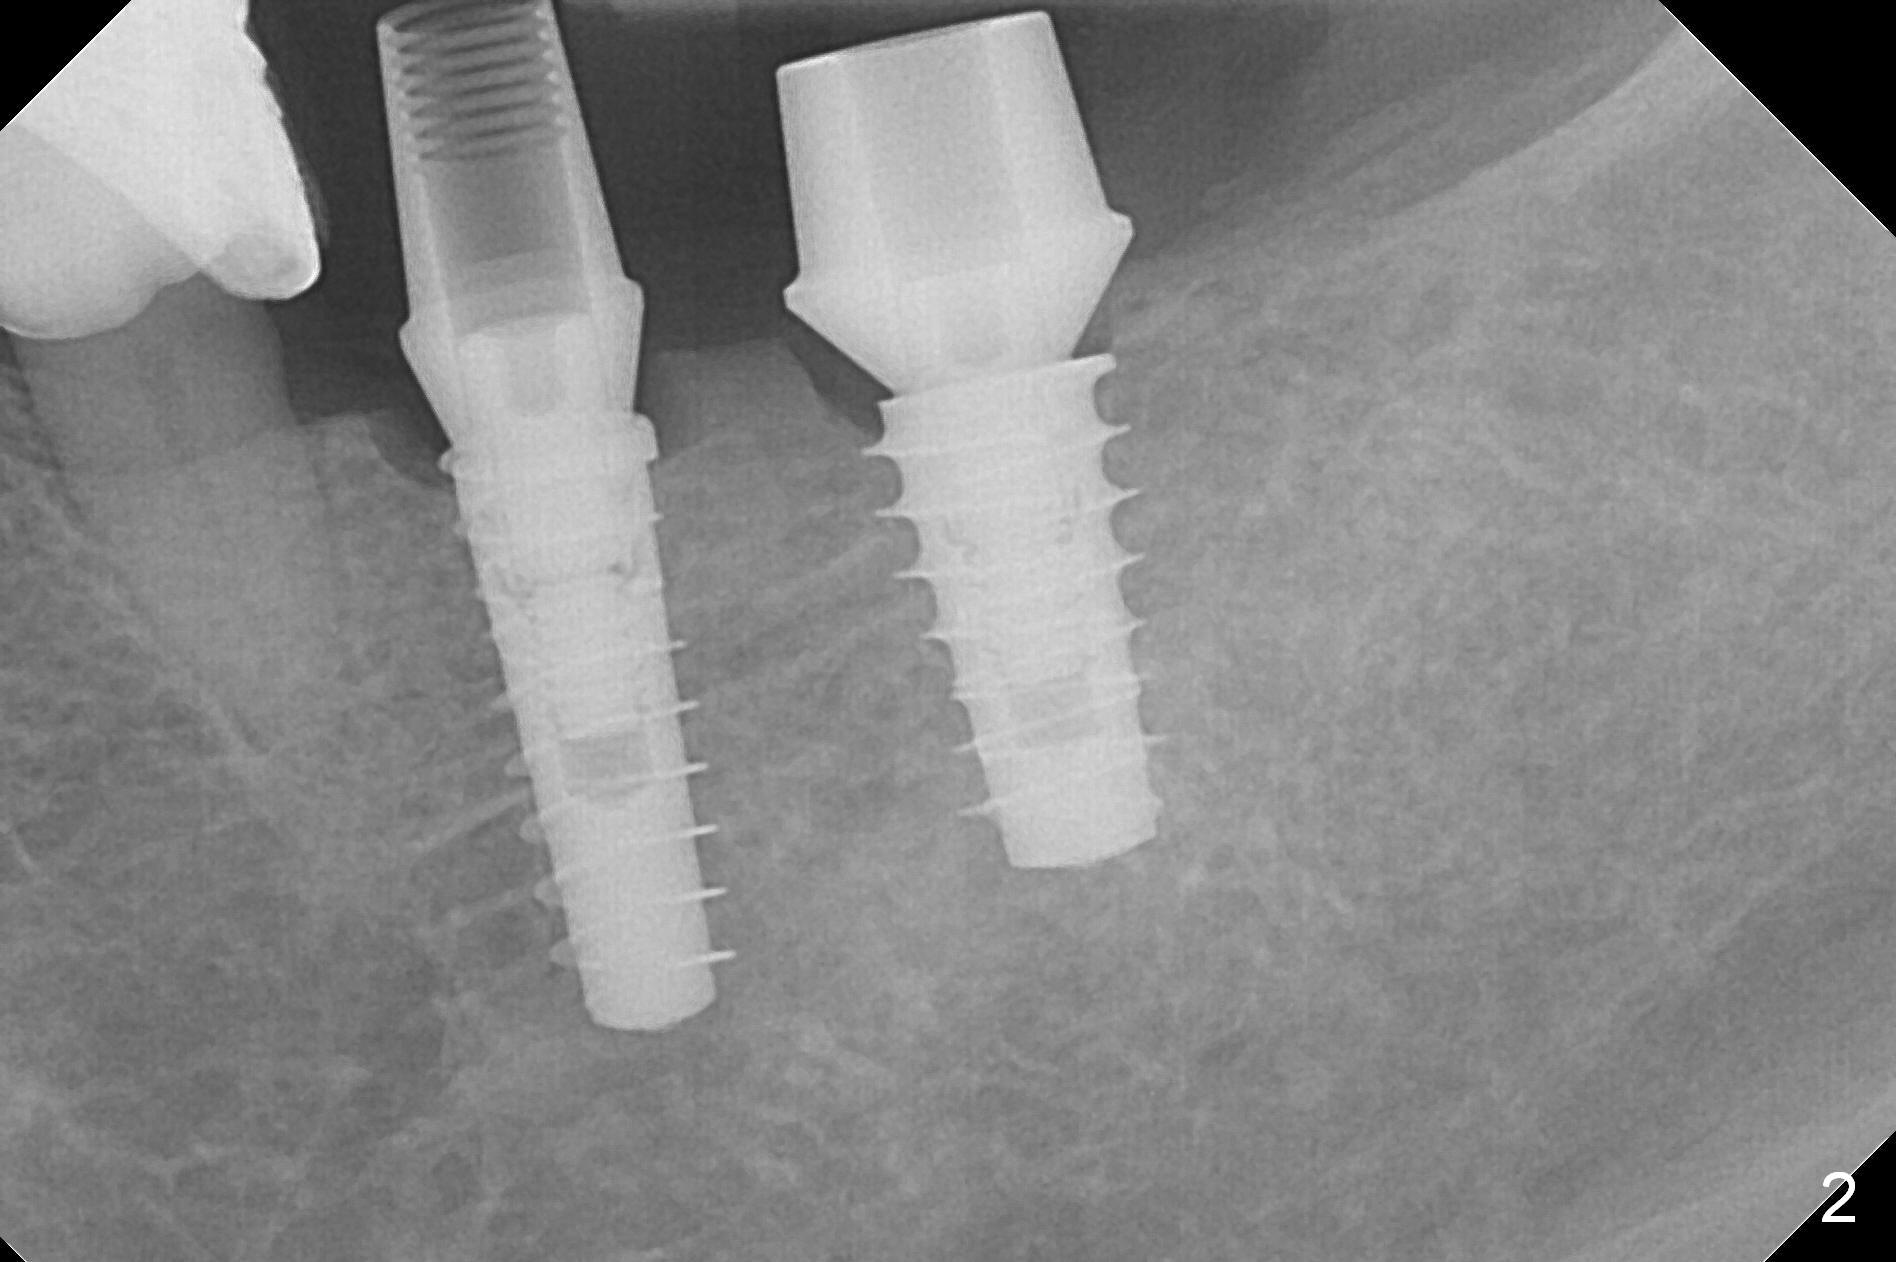

Because of the narrow ridge top at the sites of #19 and 18, it is reduced (Fig.1 arrowheads) prior to initial osteotomy with 1.6 mm pilot drill. After Magic Drills (3.3 and 4.3 mm at #19 and 18, respectively), 4x11 and 5x9 mm IBS implants are placed with insertion torque >35 Ncm with immediate placement of pair abutments (4.5x5.7(2) and 6.5x4(2) mm, Fig.2). In fact these sites are converted to a premolar and a 1st molar (because narrow ridge at #19). Following GBR and suturing, periodontal dressing is applied around the abutments for increased retention. The regional ridge reduction makes Marking Bur unnecessary (because of flat ridge top and the soft bone in this case) and more importantly there is no thread exposure upon implant placement. The trimmed site (concavity) is favorable for bone graft and membrane placement. One month postop, loose perio dressing is removed and replaced by a splinted nonfunctional provisional. The implant sites look normal nearly 3 months postop; there is no bone loss (Fig.3). Impression is taken. The crown/abutment at #18 is loose 3 years 2 months post cementation; when the crown/abutment is retightened, the abutment remains incompletely seated (Fig.4 <) in spite of reduction of the proximal contact (arrow). It may be due to the block of the distal crest (*). After use of 5.5 mm profile drill, the 6.5x4(2) mm abutment remains unseated (Fig.5). The smaller one (5x4(2) mm, Fig.6) is seated. When the redo crown is cemented, the surrounding gingiva is healthy with a short papilla between the implant crowns (Fig.7).